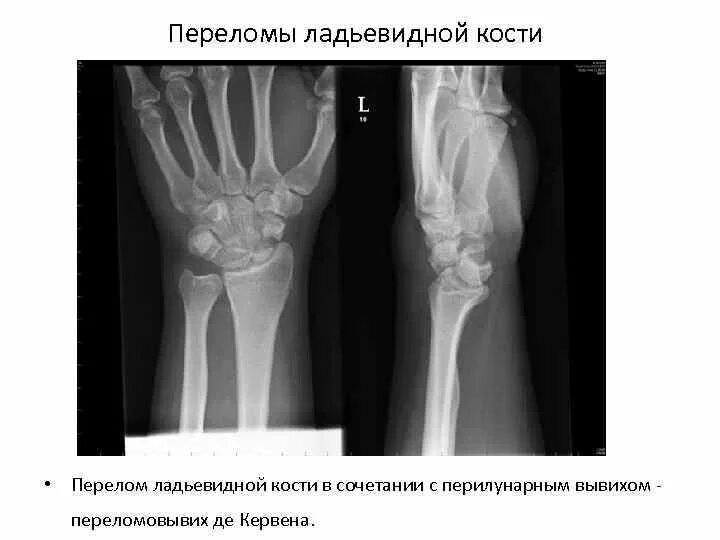

Растяжение связок лучезапястного мкб 10